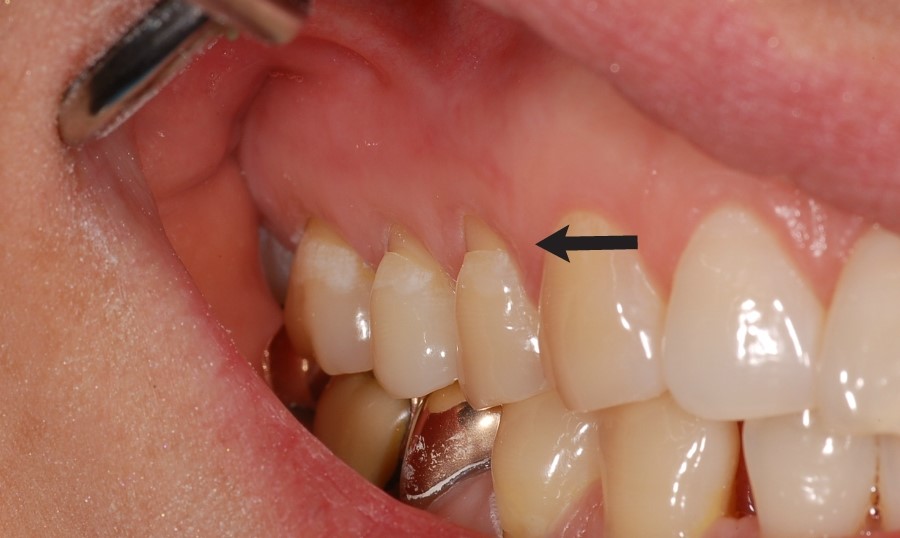

치경부 마모증

Before

치아의 치경부(잇몸과 닿아있는 부위)가 칫솔 등에 의해 마모된 경우 치료한 사례입니다.